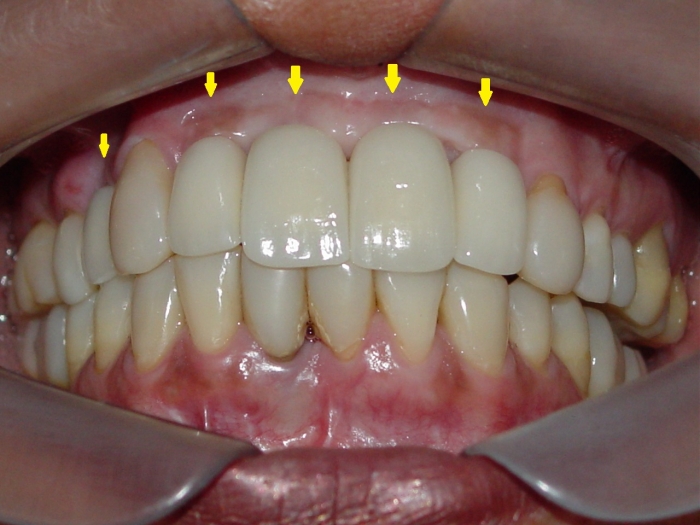

Imagem final

Sorriso final, do caso terminado em novembro de 2013